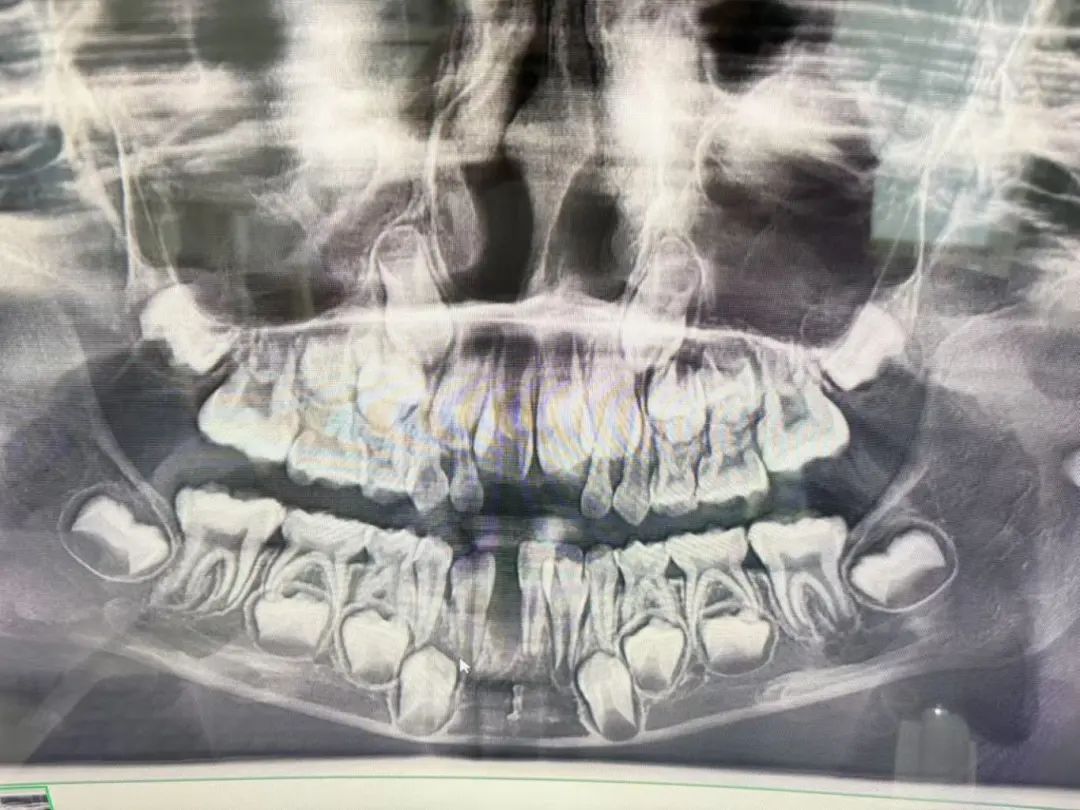

“这颗牙很难拔,拔了很长时间,最后医生拿出来的牙齿是很长的一颗,为此,我觉得很奇怪。孩子告诉我,拔牙后很疼。”孟女士说,医生随后带着孩子去照了一个片,并告诉她,孩子天生缺失恒牙,对此她也不太懂。

记者从孟女士提供的两张照片上看到,第一张照片上的牙齿是完整的,第二张照片上则有一颗牙不见了,而应该拔掉的那颗牙还在。